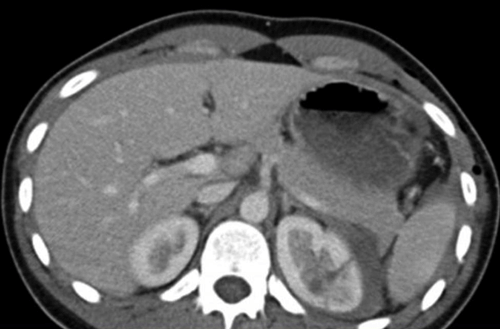

A 29-year-old male was attacked and kicked in his left flank. He presented to the emergency department with left flank pain and frank haematuria. He remained haemodynamically stable.

1. Renal trauma. CT scan with intravenous contrast and delayed excretory imaging.

2. Blunt trauma with visible haematuria (visible or non-visible in paediatric patients). Blunt trauma with non-visible haematuria with hypotension, or the presence of major associated injuries. Rapid deceleration injury. Penetrating trauma regardless of haematuria.

3. The American Association for the Surgery of Trauma (AAST) renal trauma severity scale.

Grade 1

Description of injury: Contusion or non-expanding subcapsular haematoma. No laceration.

Grade 2

Description of injury: Non-expanding peri-renal haematoma. Cortical laceration <1cm deep without extravasation

Grade 3

Description of injury: Cortical laceration >1cm deep without urinary extravasation.

Grade 4

Description of injury: Laceration: through corticomedullary junction into collecting system; or Vascular: segmental renal artery or vein injury with contained haematoma, or partial vessel laceration, or vessel thrombosis.

Grade 5

Description of injury: Laceration: shattered kidney; or Vascular: renal pedicle or avulsion.